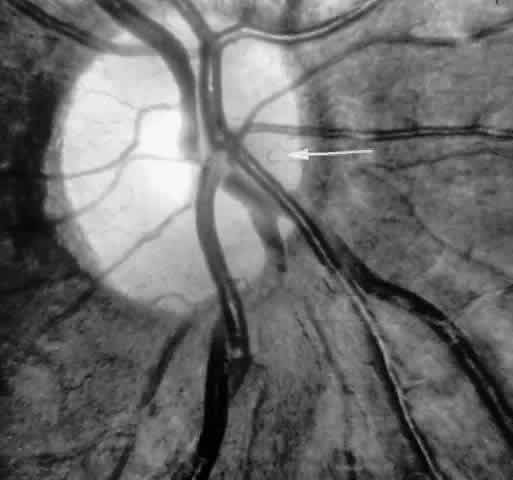

Occlusions of the fine vasculature of the macular and perimacular area have been reported in 10% to 40% of patients with sickle cell disease.18,83,91–99 In the acute phase, the occluded vessel will have a dark red appearance and may appear as a dark line on fluorescein angiography (Fig. 9). Nerve fiber layer infarcts (cotton-wool spots) are seen (see Fig. 8D and E;Fig. 10).100

Fig. 9. A 27-year-old man with homozygous sickle cell anemia. A. Fluorescein angiogram of the right eye shows multiple arteriolar occlusions temporal to the fovea (arrows). B. Same area 6 months later shows more extensive occlusions. The black arrowheads (A and B) identify corresponding arteriolar bifurcation.

Fig. 10. A 33-year-old woman with SC disease and stage III sickle cell retinopathy. A. Photograph of the right eye shows a cotton-wool spot with a dark segment identifying the occluded vessel (arrow). B. Fluorescein angiogram demonstrates nonfilling of the occluded vessel (arrow). C. Eighteen months later, the occluded vessel is still visible (arrow). D. Fluorescein angiogram demonstrates that there is still nonfilling of the vessel (arrow).